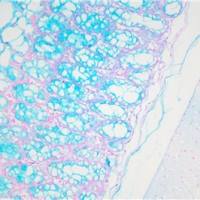

免疫组化是应用免疫学基本原理——抗原抗体反应,即抗原与抗体特异性结合的原理,通过化学反应使标记抗体的显色剂(荧光素、酶、金属离子、同位素) 显色来确定组织细胞内抗原(多肽和蛋白质),对其进行定位、定性及定量的研究,称为免疫组织化学技术(immunohistochemistry)或免疫细胞化学技术(immunocytochemistry)。

免疫组化的分类: 免疫组织化学技术按照标记物的种类可分为免疫荧光法、免疫酶法、免疫铁蛋白法、免疫金法等。

服务内容:包含抗体,包埋,切片,染色以及拍照。(每个样本提供一张照片包含阳性面积)加拍另外计费